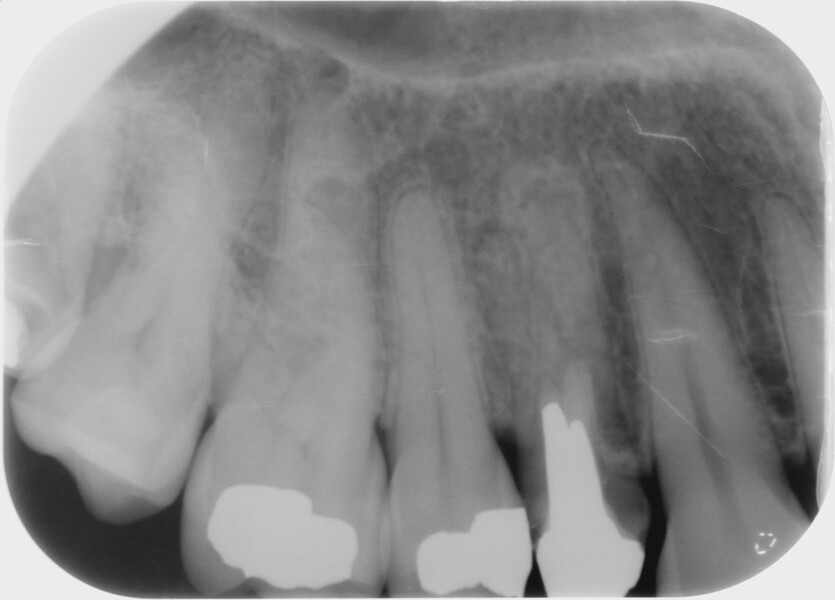

Fig. 3 : Contrôle radiographique après la finition de la prothèse.

D’un point de vue pratique, la première étape consiste à réduire les dimensions du tenon s’il occupe une grande partie de la structure coronaire, de préférence en lui donnant une forme cylindrique similaire à celle d’un tenon préfabriqué. De même, une reconstitution corono-radiculaire coulée ancrée dans plusieurs canaux doit d’abord être sectionnée jusqu’au niveau du plancher de la cavité pulpaire, afin de la traiter comme un ensemble de tenons unitaires, ce qui diminue le degré de rétention global du système. La réduction du tenon doit être effectuée avec des fraises en carbure spécialement conçues pour découper le métal, sous une irrigation abondante. Les évaluations cliniques et radiographies préliminaires sont essentielles pour planifier l’angle de coupe. La procédure doit être fréquemment vérifiée et, si nécessaire, il convient d’effectuer des contrôles radiographiques avant qu’une quantité excessive de dentine ne soit sacrifiée (Figs. 1–3).